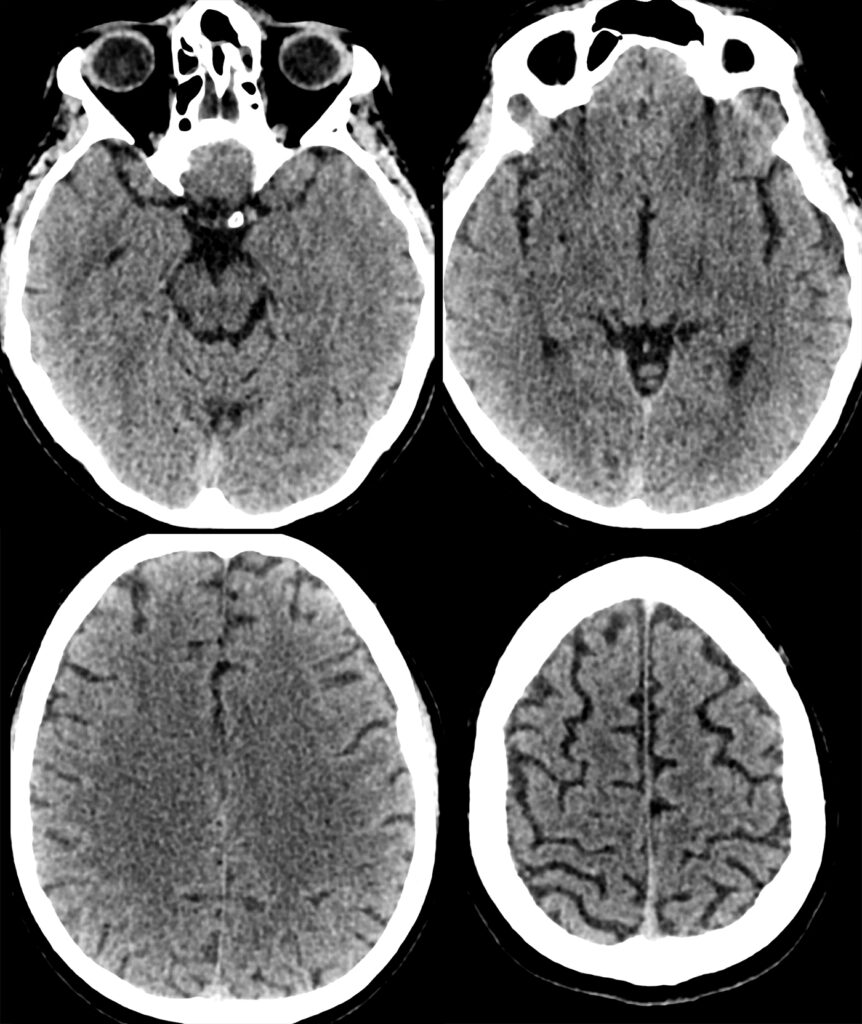

What abnormalities if any can you see?

Now 4 hours 40 mins (280 mins) since diplopia, BP currently 190/100, NIHSS unchanged at 13.